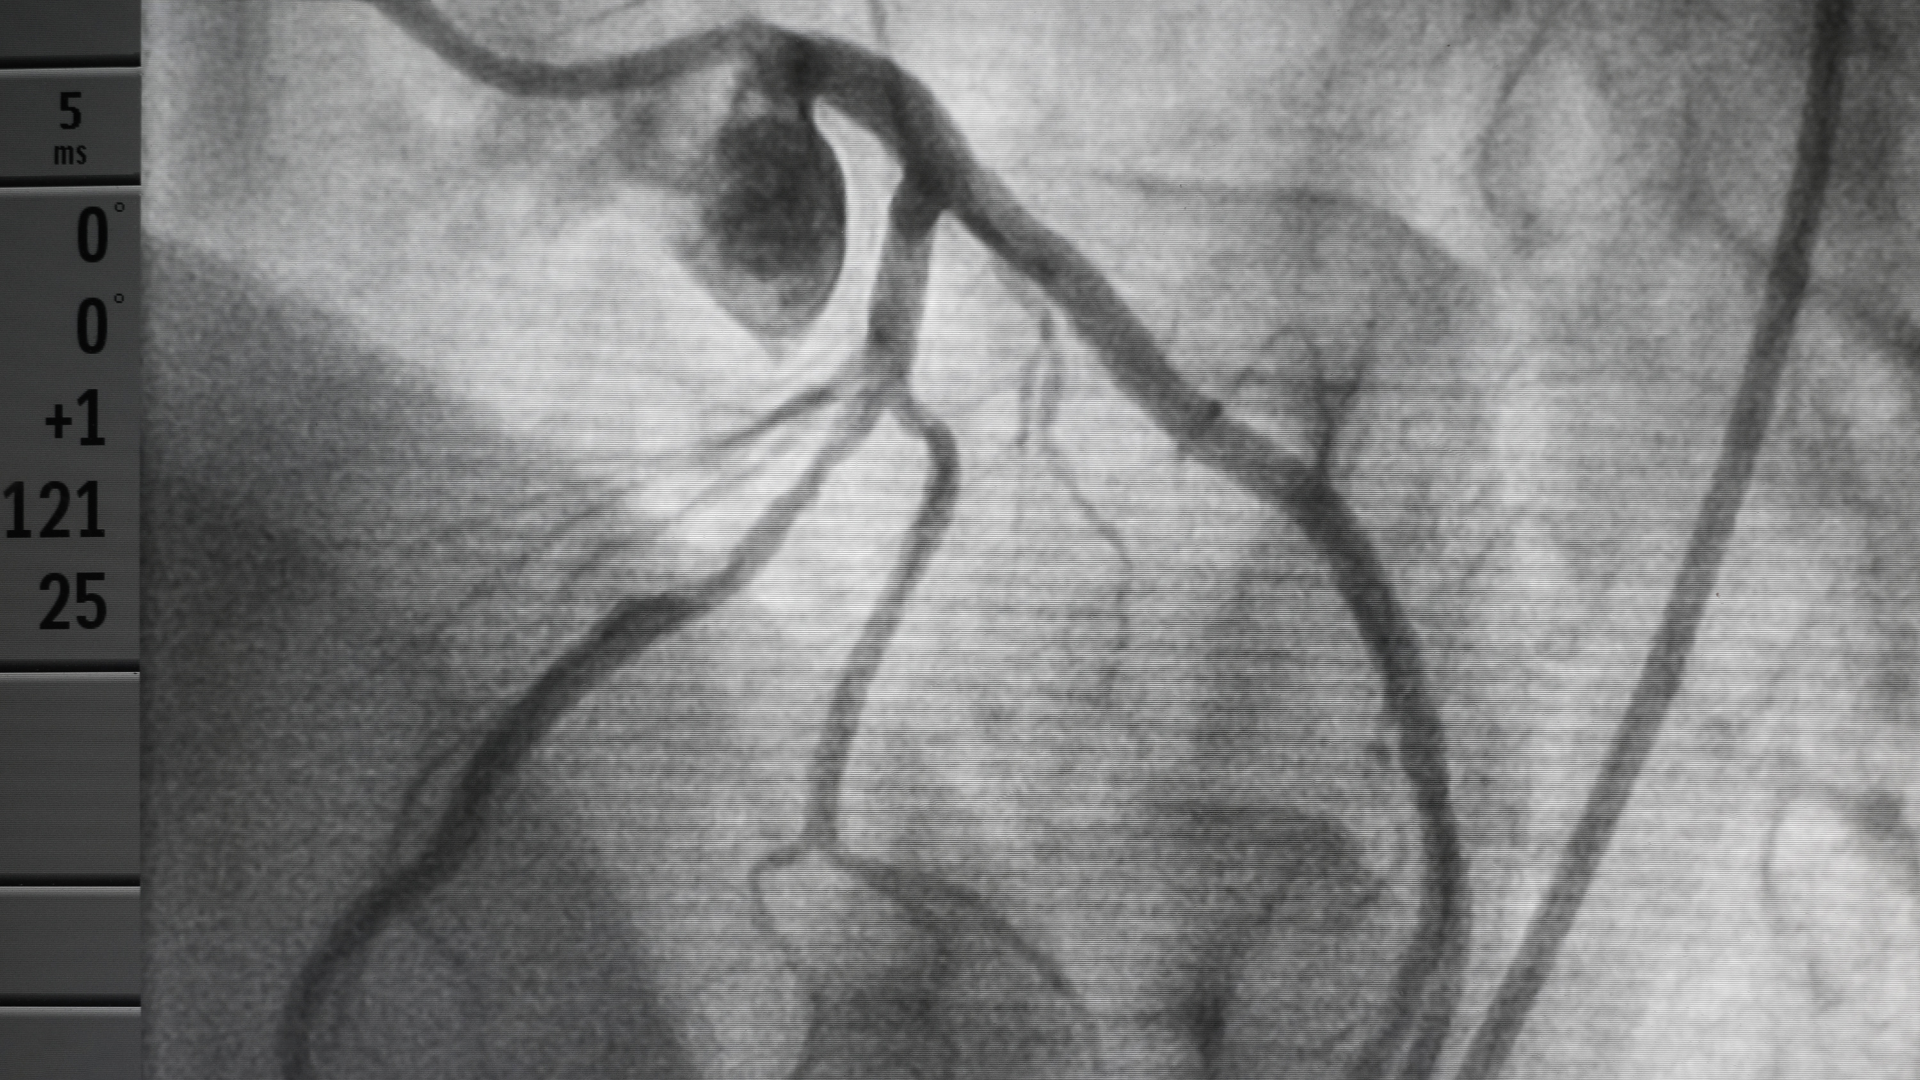

Coronary Angiogram

This is a test where the heart arteries can be directly visualised by an X-ray. Under local anaesthetic a tube is passed via the artery in the wrist or leg into the heart, and dye injected into the heart arteries. This is still the best way of establishing whether there is any narrowing of the heart arteries.